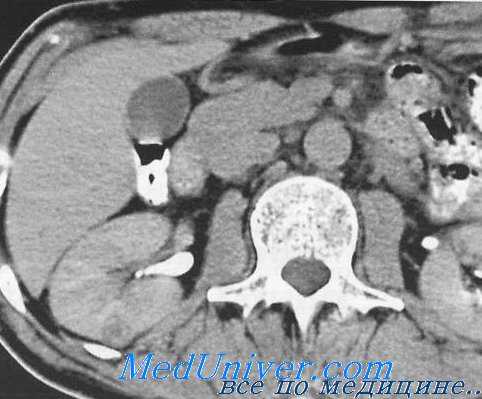

Абдоминальная компьютерная томография. Предостережения при обследовании хирургических больных.

Использование компьютерной томографии (КТ) в диагностике острого живота остается предметом споров. Пока КТ не входит в алгоритм обследования большинства пациентов с острыми болями в животе, однако новая технология — спиральная КТ, когда она доступна для срочных исследований, обладает большой разрешающей способностью и представляет определенный соблазн для не очень опытных клиницистов.

Особенно это касается острого дивертикулита. Если клинические проявления местного перитонита в левом нижнем квадранте живота идентифицированы, то начинают лечение с консервативных мер. КТ может показать воспалительный процесс и даже околокишечный гнойник, но не поможет отличить дивертикулит от перфорации опухоли толстой кишки. Во всяком случае в подобных клинических ситуациях КТ не является обязательным исследованием, так как независимо от результатов КТ большинство хирургов начинают лечение с внутривенного введения антибиотиков.

Истинное значение компьютерной томографии, когда она действительно может сыграть решающую роль, проявляется в «клинических головоломках». Нередко хирург встречается с острой болью в животе, которая никак не укладывается в ситуации, описанные в предыдущей главе. При вполне очевидном плохом состоянии больного диагноз остается неясным. Порой острая внутрибрюшная патология может быть заподозрена у пациента в бессознательном состоянии. В этих обстоятельствах КТ может очень помочь в разрешении абдоминальной проблемы и даже исключить ее (абсолютно нормальная КТ). Это исследование часто показано больным после тупой (закрытой) травмы живота), оно играет определенную роль в послеоперационном периоде. Избирательное использование КТ в других обстоятельствах рассмотрено в последующих главах.